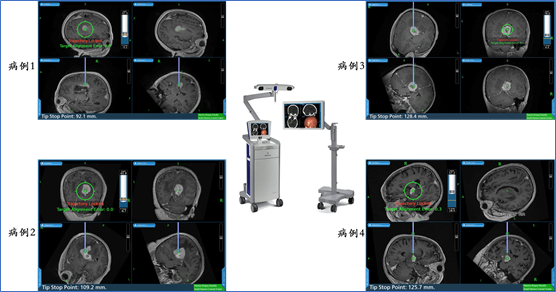

2. 神经导航下颅内病灶活检术目的:取得肿瘤组织,明确病理诊断、分子病理诊断、指导后续治疗方案;

适应症: 无法或需要明确(分子)病理的绝大多数脑转移病人。

立体定向活检手术病例